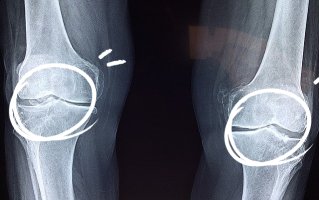

보통 사람의 연골은 60%~80%가 수분으로 구성되어 있고 그 밖에 콜라겐, 글루코사민, 콘드로이친, 히알루론산으로 이루어져 있습니다. 이 중 콘드로이친은 연골의 수분을 유지해 주고 뼈와 연골과 같은 조직을 형성하며 구성하는 성분입니다. 나이가 들어감에 따라 감소하는 콘드로이친은 20대부터 서서히 줄어들기 시작해 40대가 되면 20대의 절반으로 줄어들고 70대가 되면 75%가 줄어들면서 시간이 지나면 점점 더 없어진다고 합니다.

콘드로이틴은 연골에서 발견되는 가장 두드러진 물질입니다. 그것은 무릎의 골관절염 환자에게 도움이 될 수 있는 분해로부터 세포를 보호하고 유지함으로써 기능합니다. 여러 연구에 따르면 연골 손실률도 개선할 수 있습니다.

콘드로이친 효능으로 관절 통증을 줄여주는 것이 대표적인 효능인데 이 콘드로이친은 보통 관절염으로 인한 통증 완화와 전반적인 관절 건강을 위해 사람들이 많이 찾는 성분입니다. 관절염의 증상을 완화시켜 줄 수는 있지만 섭취로 인한 효과가 오래 지속되지는 않는 단점이 있습니다.